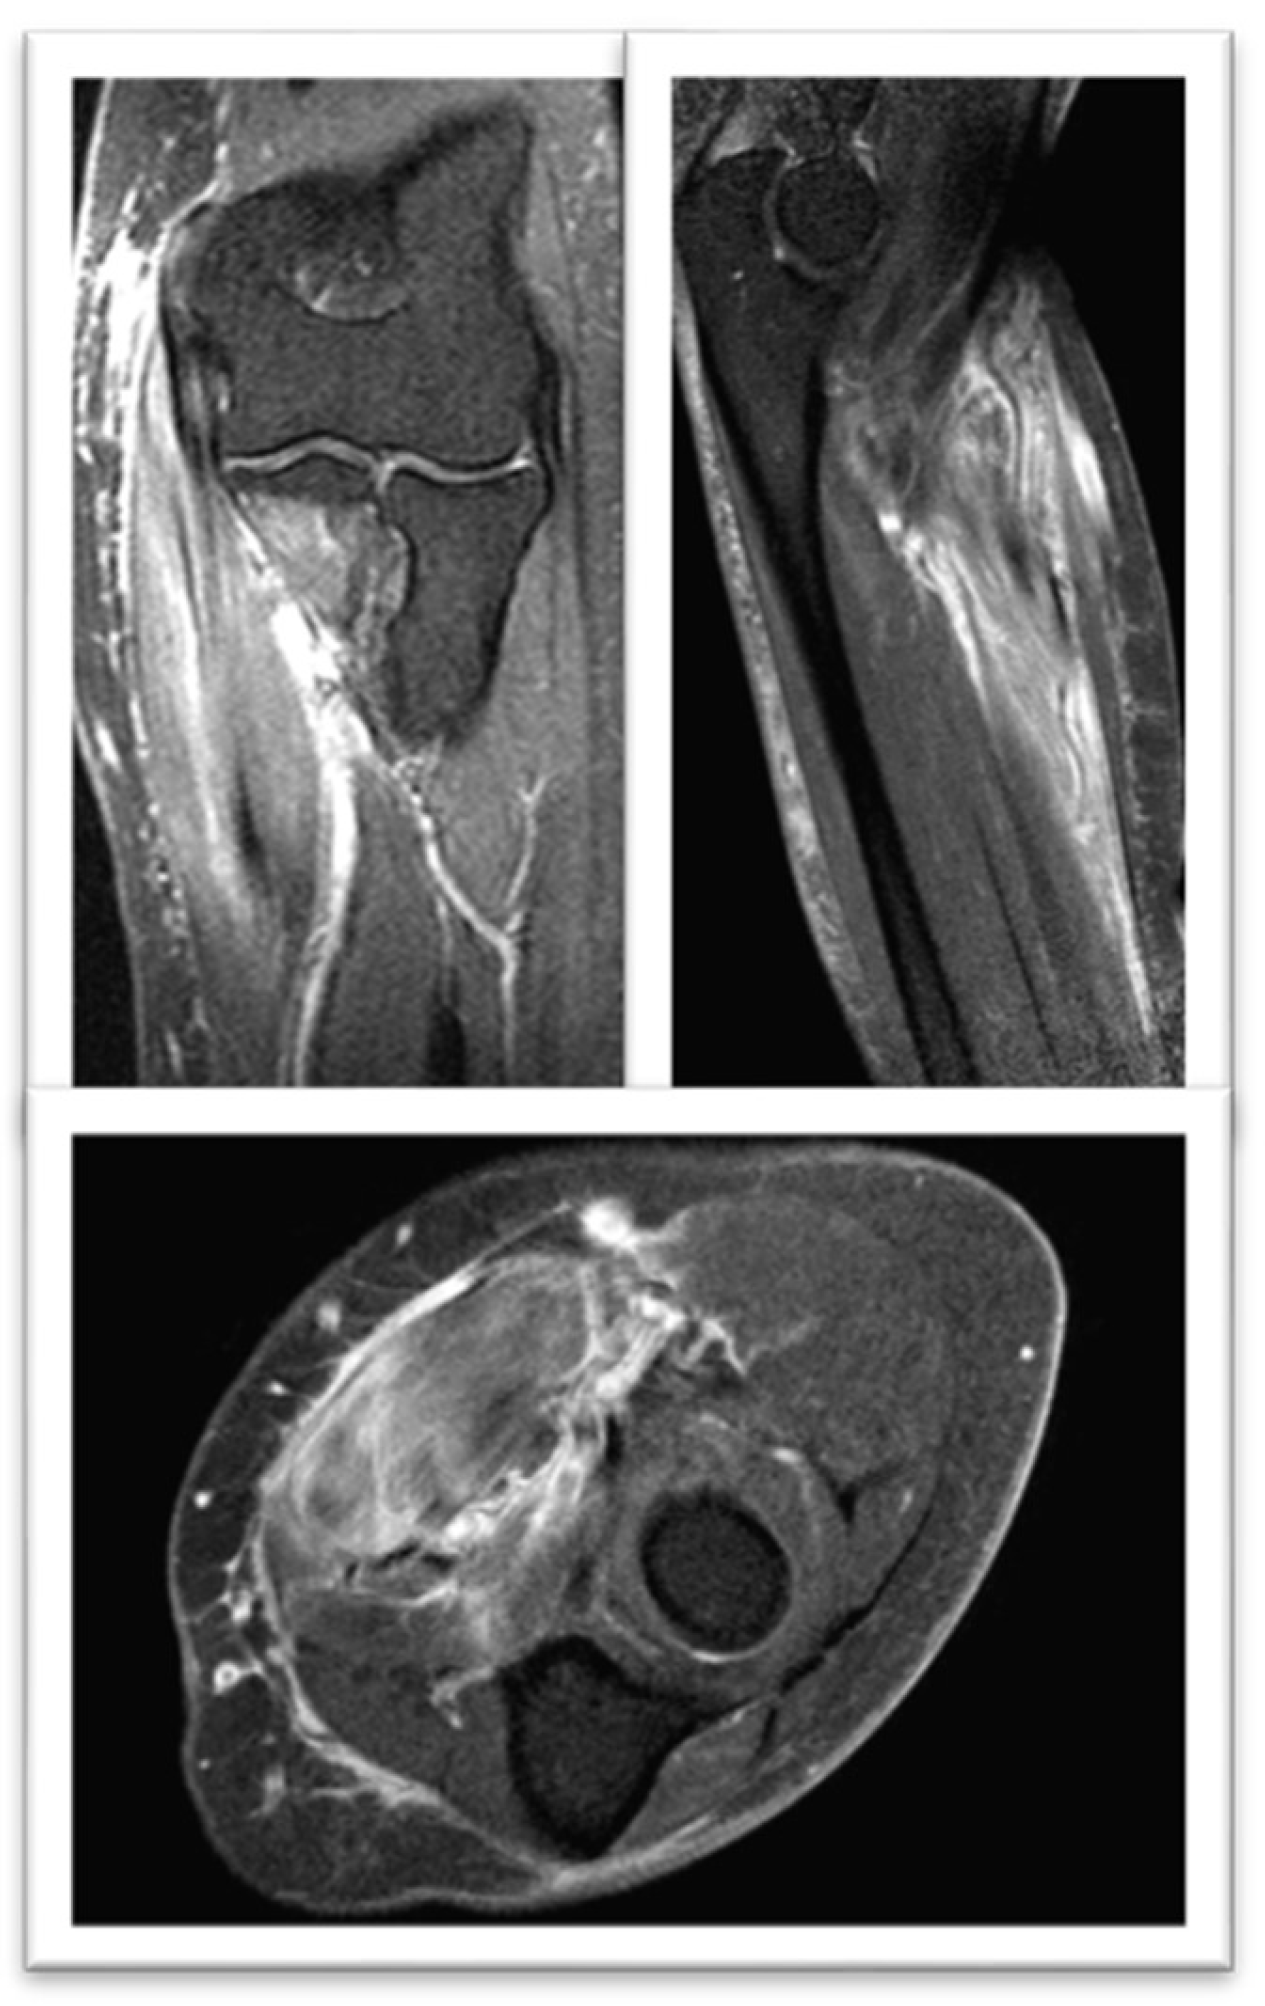

Magnetic Resonance Nuclear: Signal alteration with enhancement mainly in the flexor carpi radialis muscle. Findings in relation to myositis (Figure 3).

Given the diagnostic criteria of IMNM secondary to statins, it was decided to withdraw cholesterol-lowering treatment. After three months, despite the improvement in his symptoms, and the altered signal in the affected muscles in the control MRI (Figure 4), the persistence of muscle weakness did not improve and the CK values increased, so Treatment was started with prednisolone 1 mg/kg/day.

Figure 3. FSE STIR MRI of the left thigh in coronal view demonstrating patchy feathery STIR signal intensity seen throughout the left proximal third of the left brachioradialis muscle.

Figure 4. FSE STIR MRI of the left thigh in coronal view at three months treatament, demonstrating normal STIR signal intensity seen throughout the left proximal third of the left brachioradialis muscle.